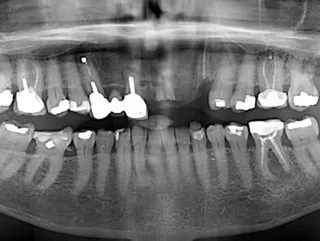

• Radiographie préopératoire

• Radiographie périapicale lors du suivi à 6 mois